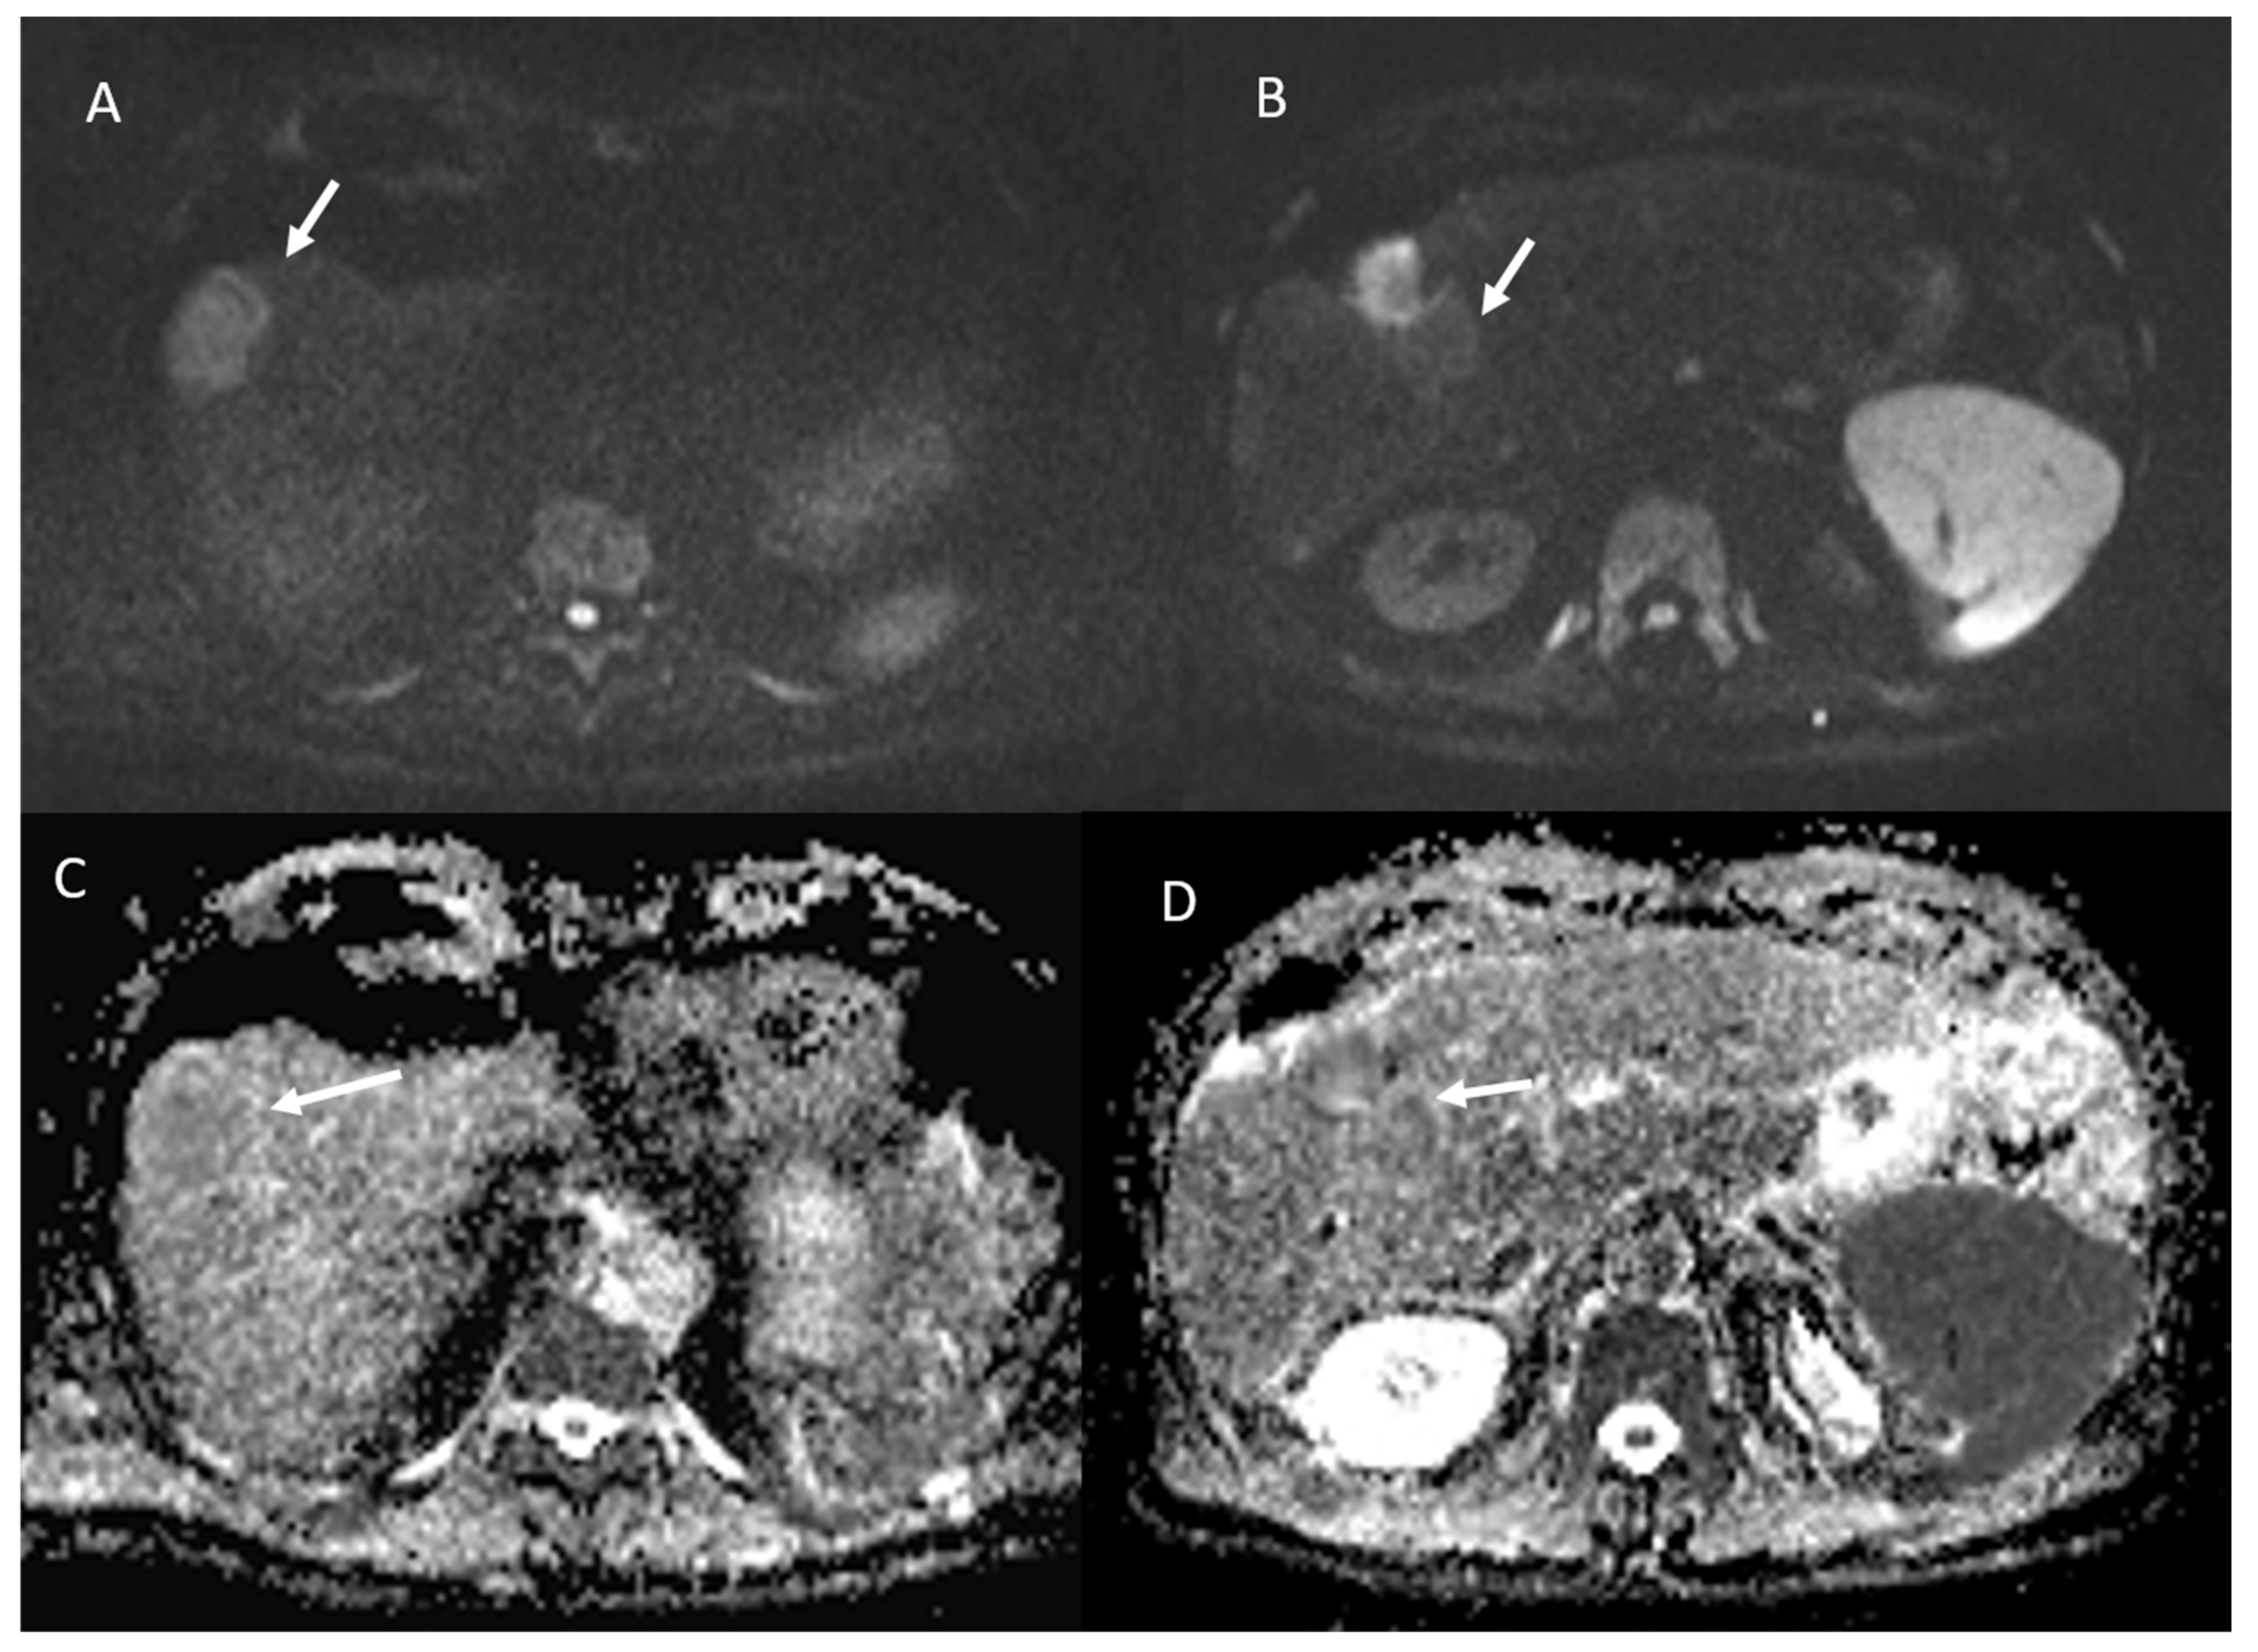

- 23 lesions showed restricted diffusion with hypointense SI in ADC map (Figure 4).

- 84 lesions showed restricted diffusion (Figure 7) with iso-hypointense in ADC map and 29 showed no restricted diffusion.